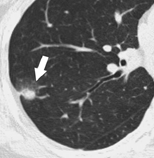

按照CT图像上结节密度的不同,结节分为实性结节和亚实性结节,而亚实性结节又分为部分实性结节和磨玻璃密度结节。实性结节是指看起来和人体软组织密度相似的病灶;磨玻璃密度结节是指肺内模糊的、半透明的结节影;而部分实性结节是指其内既有模糊的部分又有较高密度部分的病灶。在实性结节、部分实性结节和磨玻璃密度结节中,部分实性结节的恶性概率是最高的。

磨玻璃结节 部分实性结节 实性结节